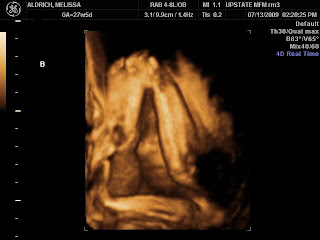

- Baby B is my camera hogging diva. She even put her feet in front of Baby A’s head to block a decent head shot.

It was a good visit AND we got 3D ultrasound photos! I love how they are fascinated with their feet though it proved difficult to get face shots with all those feet. By the way, Baby B’s feet are the ones blocking Baby A’s shot. She did not want her sister to have the limelight!